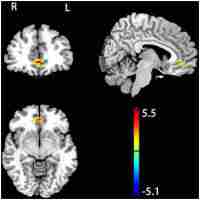

| Abstract | Working memory refers to the temporary maintenance and processing of information and involves executive processes that manipulate the contents of the working memory. The role of the executive function in the human left dorsolateral prefrontal cortex (LDLPFC) was explored using transcranial magnetic stimulation (TMS) after confirming the LDLPFC activation using fMRI. We applied double-pulse TMS having a 100-ms inter-pulse interval to LDLPFC immediately after the subjects finished reading the sentences of the reading span test (RST) task, an efficient measure of verbal working memory, in which dual tasks that include both sentence comprehension and word maintenance are required. Using eight normal participants, we found a significant deterioration of performance, i.e., decreased number of correctly reported words, in RST due to TMS stimulation of LDLPFC. Evidence suggests that transient functional disruption of the LDLPFC impairs performance in the maintenance processing of the RST task. |